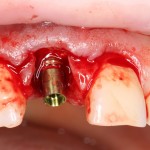

По ряду причин, мы вынуждены удалить верхнюю шестерку и заменит ее на имплантат.

Все начинается с удаления зуба:

Обратите внимание на состояние вестибулярной стенки лунки. В проекции верхушек корней вы можете увидеть костный дефект, вызванный длительным воспалительным процессом (собственно, почему этот зуб пришлось удалять). В этом случае, вестибулярная стенка лунки неизбежно лизируется после удаления зуба, а это приведет не только к проблемам в эстетике, но и осложнит последующий уход за протетической конструкцией. Поэтому в данном случае мы должны продумать, в том числе, аугментацию лунки. И порядок действий здесь несколько иной, нежели в предыдущем случае.

Устанавливается имплантат Astratech (Dentsply Implants):

Для аугментации также используем Bio-Oss Collagen 100 mg, нарезаем его по размеру с помощью скальпеля и позиционируем в лунках щечных корней:

На имплантат ставим формирователь, ушиваем лунку. Напомню, что любой биоматериал должен быть герметично запечатан в ране (фактор успеха III). В противном случае, от него больше вреда, чем пользы:

Совсем уж стягивать края раны не нужно (если бы мы использовали обычный Bio-Oss, то это было бы необходимо). Отличие Bio-Oss Collagen еще и в том, что он не размывается при кровотечении.

Через неделю можно снять швы. Область раны выглядит следующим образом: